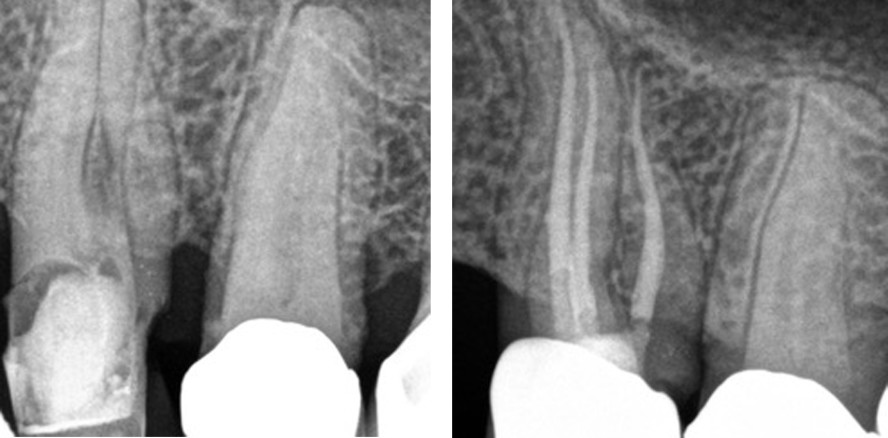

Abbildungen von rechts nach links: a) Patientenfall: Ausgangsröntgenbild; b) Masterpointaufnahme; c) Abschlussröntgenbild; d) Röntgennachkontrolle nach 6 Monaten. © Dr. Christofzik